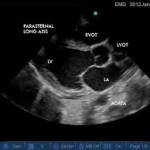

Echocardiography has now formally come of age. International position statement on echo training: what’s expected from basic and advanced practitioners, what competency means, how to properly report echo findings.